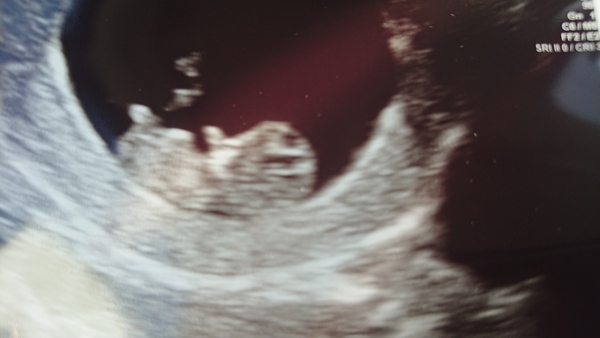

Had my scan this morning! 9+6! It actually looks like a baby!

@balalalala 😍 that's wonderful to see, it does look like a baby!

@balalalala oh my goodness what a beautiful scan! Well done for growing such a beautiful baby, clever mummy.

@balalalala that is the most perfect little teeny tiny baby I've ever seen!! And after all that worry it's given you!!! So pleased for you!

@balalalala way to make a woman cry! Absolutely stunning scan, congratulations x

Aw thanks guys! I really thought it was all over 2 weeks ago!

Such a beautiful tiny human 💙💜 xxx

Ahhh lovely scan photo @balalala